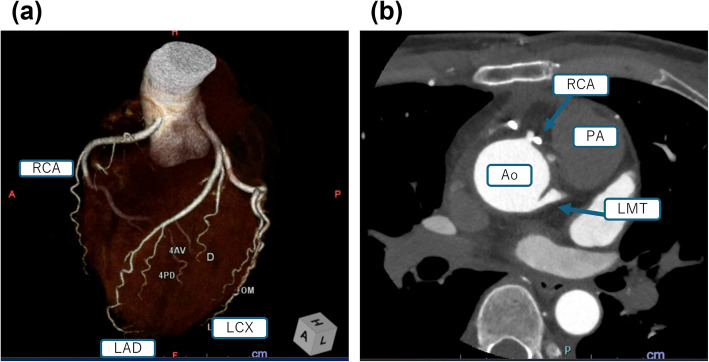

Background: Coronary artery origin anomalies, though often incidentally detected, can lead to sudden death. Comprehensive perioperative management is essential. We report a case of an anomalous right coronary artery (RCA) arising from the left main coronary artery (LMCA) and coursing between the aorta and pulmonary artery, discovered after myocardial infarction, in which intraoperative management ensured successful coronary reconstruction.

Case presentation: A 49-year-old woman presented with chest pain and ST segment elevation. Coronary angiography revealed an anomalous RCA demonstrating compressive ischemia by the aorta and pulmonary artery. Preoperatively, blood pressure was stabilized with an isosorbide dinitrate patch. Under cardiopulmonary bypass, the RCA was transected and reanastomosed to its physiological aortic position. Intraoperatively, nicorandil was administered to suppress vascular smooth muscle contraction, while five-lead ECG, transesophageal echocardiography, and operative ultrasound monitoring enabled early detection of ischemia and prevented hypertension. Postoperative ventricular premature contractions resolved by the next day, with uneventful recovery.